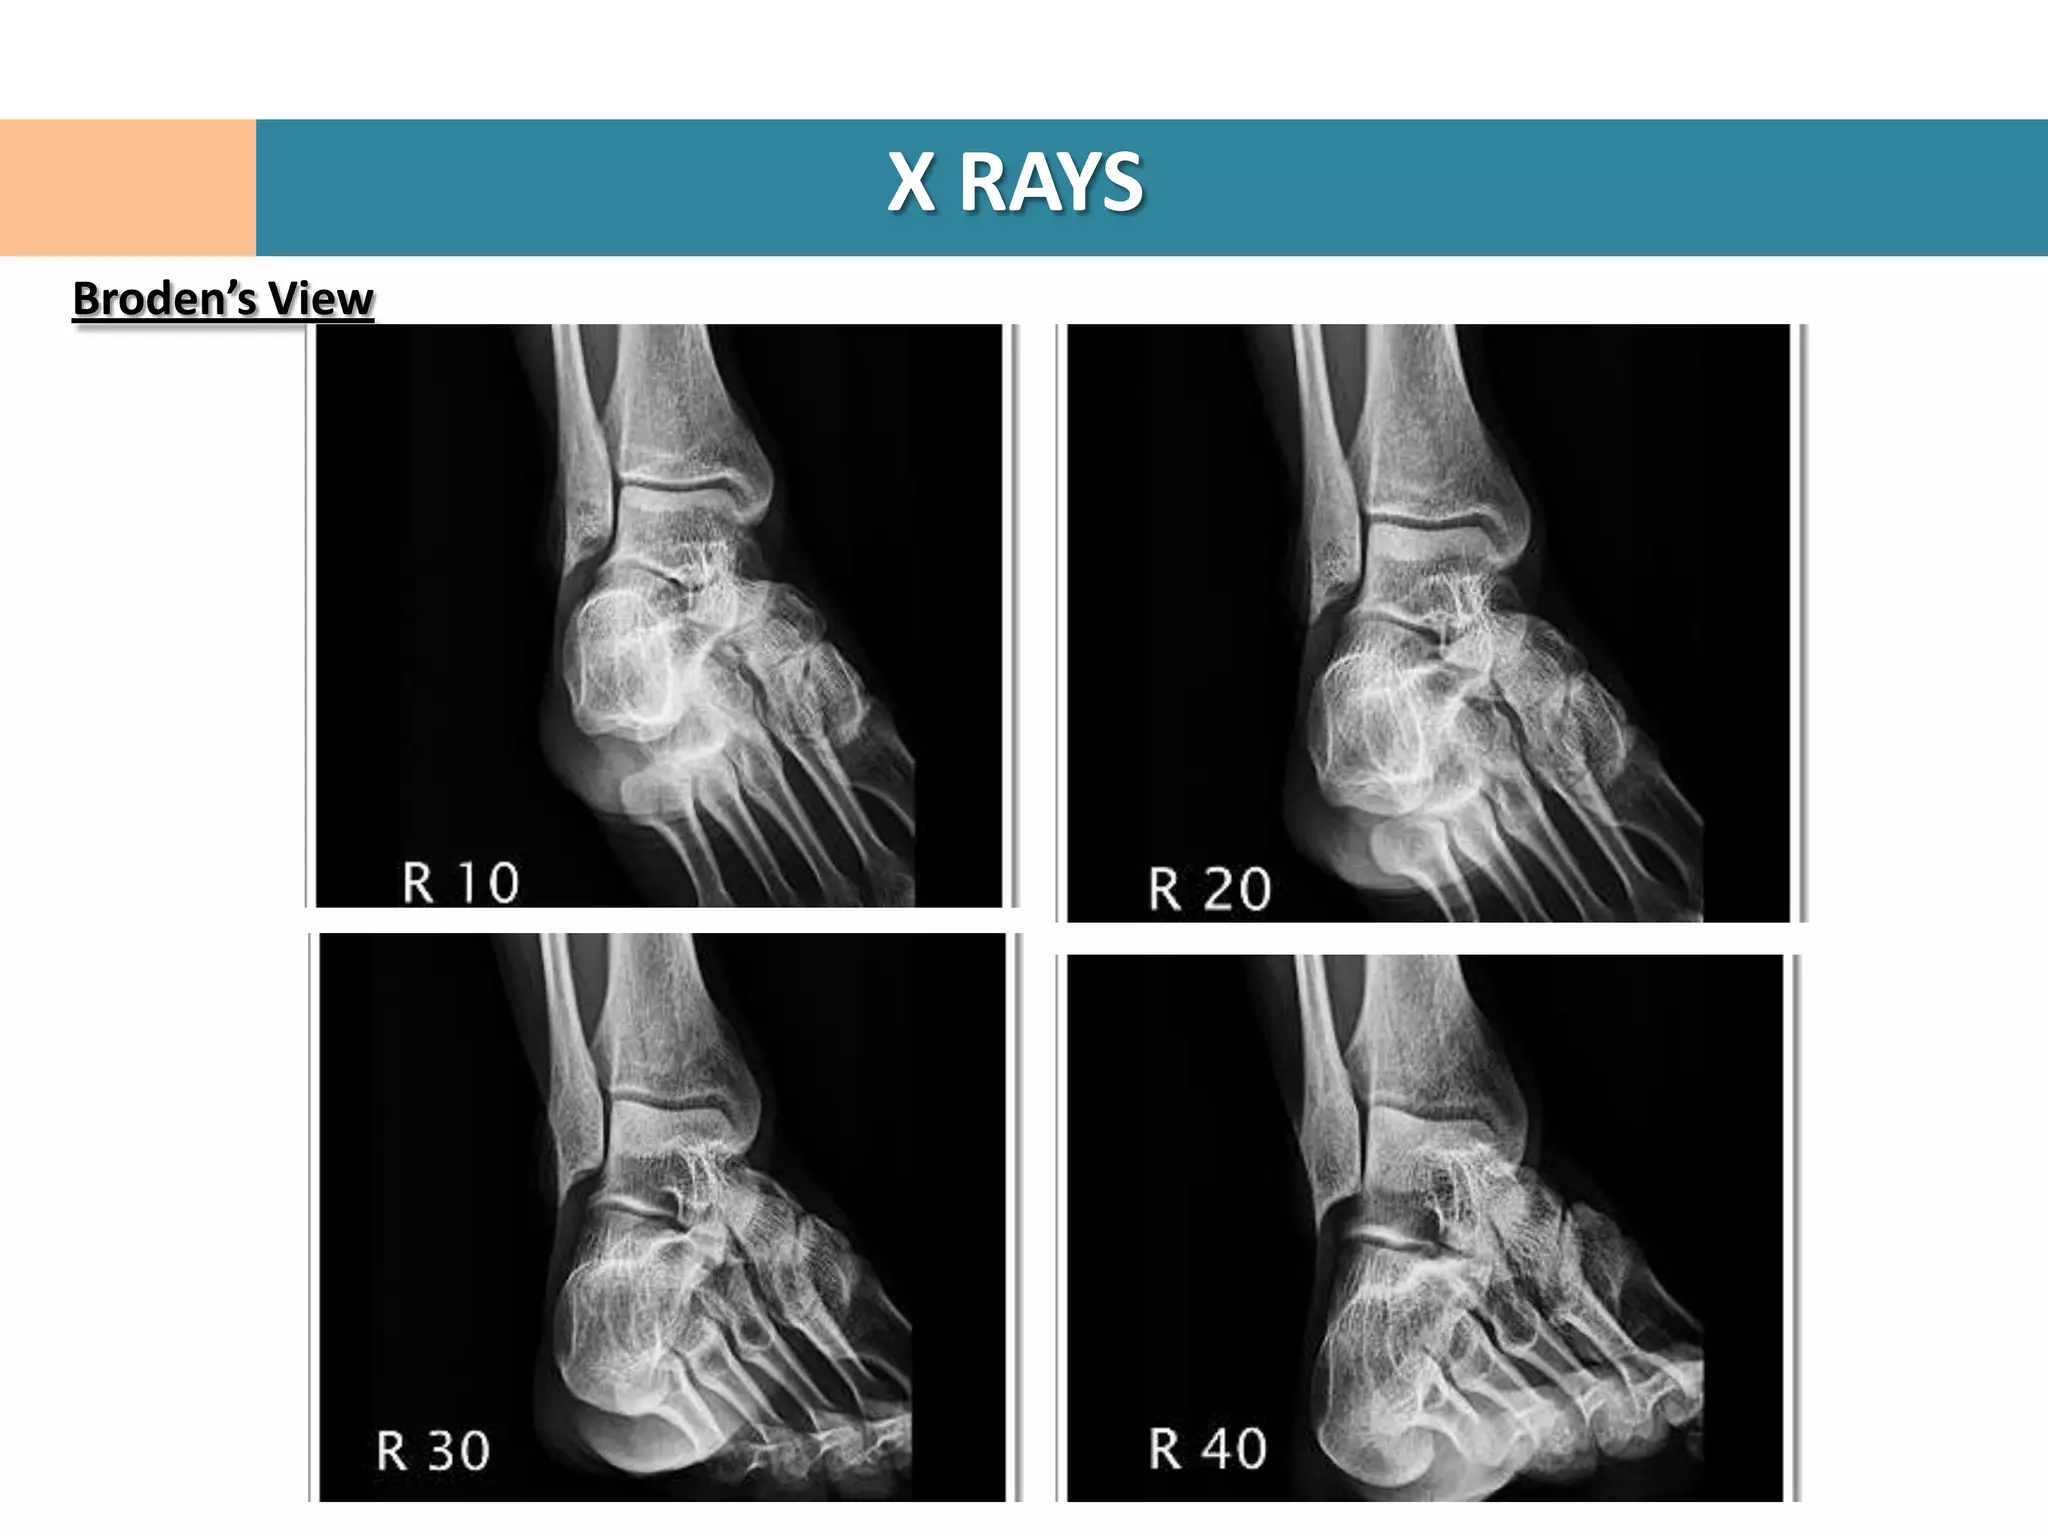

Broden’s View

Leg Internal rotated 20°

Foot Neutral

Beam directed 10/20/30/40° towards head

Centered over lateral malleolus

Demonstrates articular surface of post facet